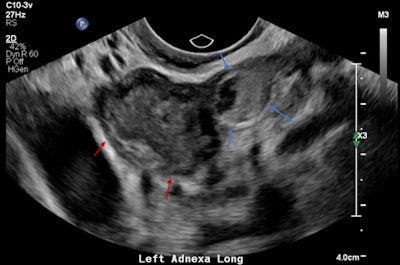

Left adnexal heterogeneous mass with an echogenic tubal ring sign (blue arrows) adjacent to the left ovary (red arrows).

Pelvic free fluid with low-level internal echoes consistent with hemoperitoneum.The patient was given a preliminary diagnosis of a hemorrhagic corpus luteal cyst. Heterotopic pregnancy was initially considered but thought less likely. The treating team opted for conservative management with a view to perform short-term follow-up ultrasound. Follow-up imaging two days later demonstrated a persistent left adnexal mass with interval increase in hemoperitoneum volume. The mass was seen to move separately to the left ovary on transvaginal/abdominal palpation maneuvers.